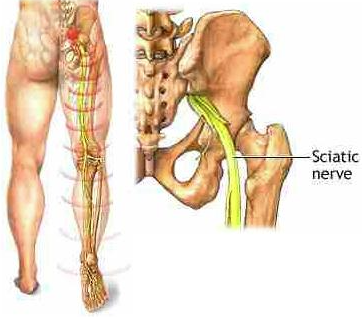

Išijas nije prava medicinska dijagnoza, ali je jedan od najčešćih problema sa leđima u današnje vrijeme. Osim jakog bola, mnogi ljudi osjećaju utrnulost, peckanje ili slabost u nogama, što može značajno otežati svakodnevni život.

Bol koji počinje u donjem dijelu leđa ili kuku i širi se niz nogu.

Peckanje ili utrnulost u nozi.

Slabost ili poteškoće u pomjeranju noge ili stopala.